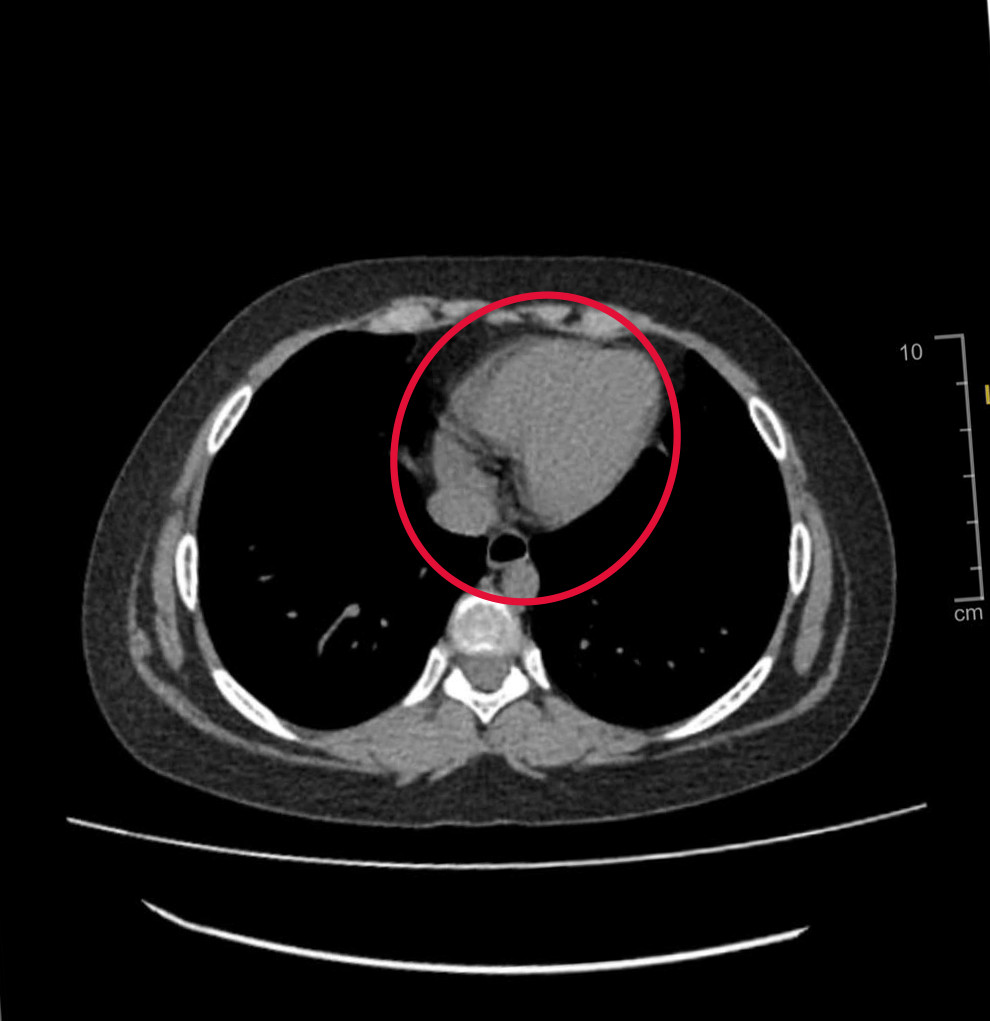

| Hình ảnh kiểm tra phát hiện khối u khiến buồng trứng của bệnh nhi bị xoắn nhiều vòng |

Sau khi tiếp nhận bệnh nhân, các bác sĩ đã khẩn trương thực hiện các bước thăm khám lâm sàng và cận lâm sàng. Kết quả kiểm tra hình ảnh cho thấy, bệnh nhi bị một khối u buồng trứng bên trái gây xoắn buồng trứng. Tình trạng xoắn buồng trứng khiến trẻ đối mặt với những cơn đau dữ dội.